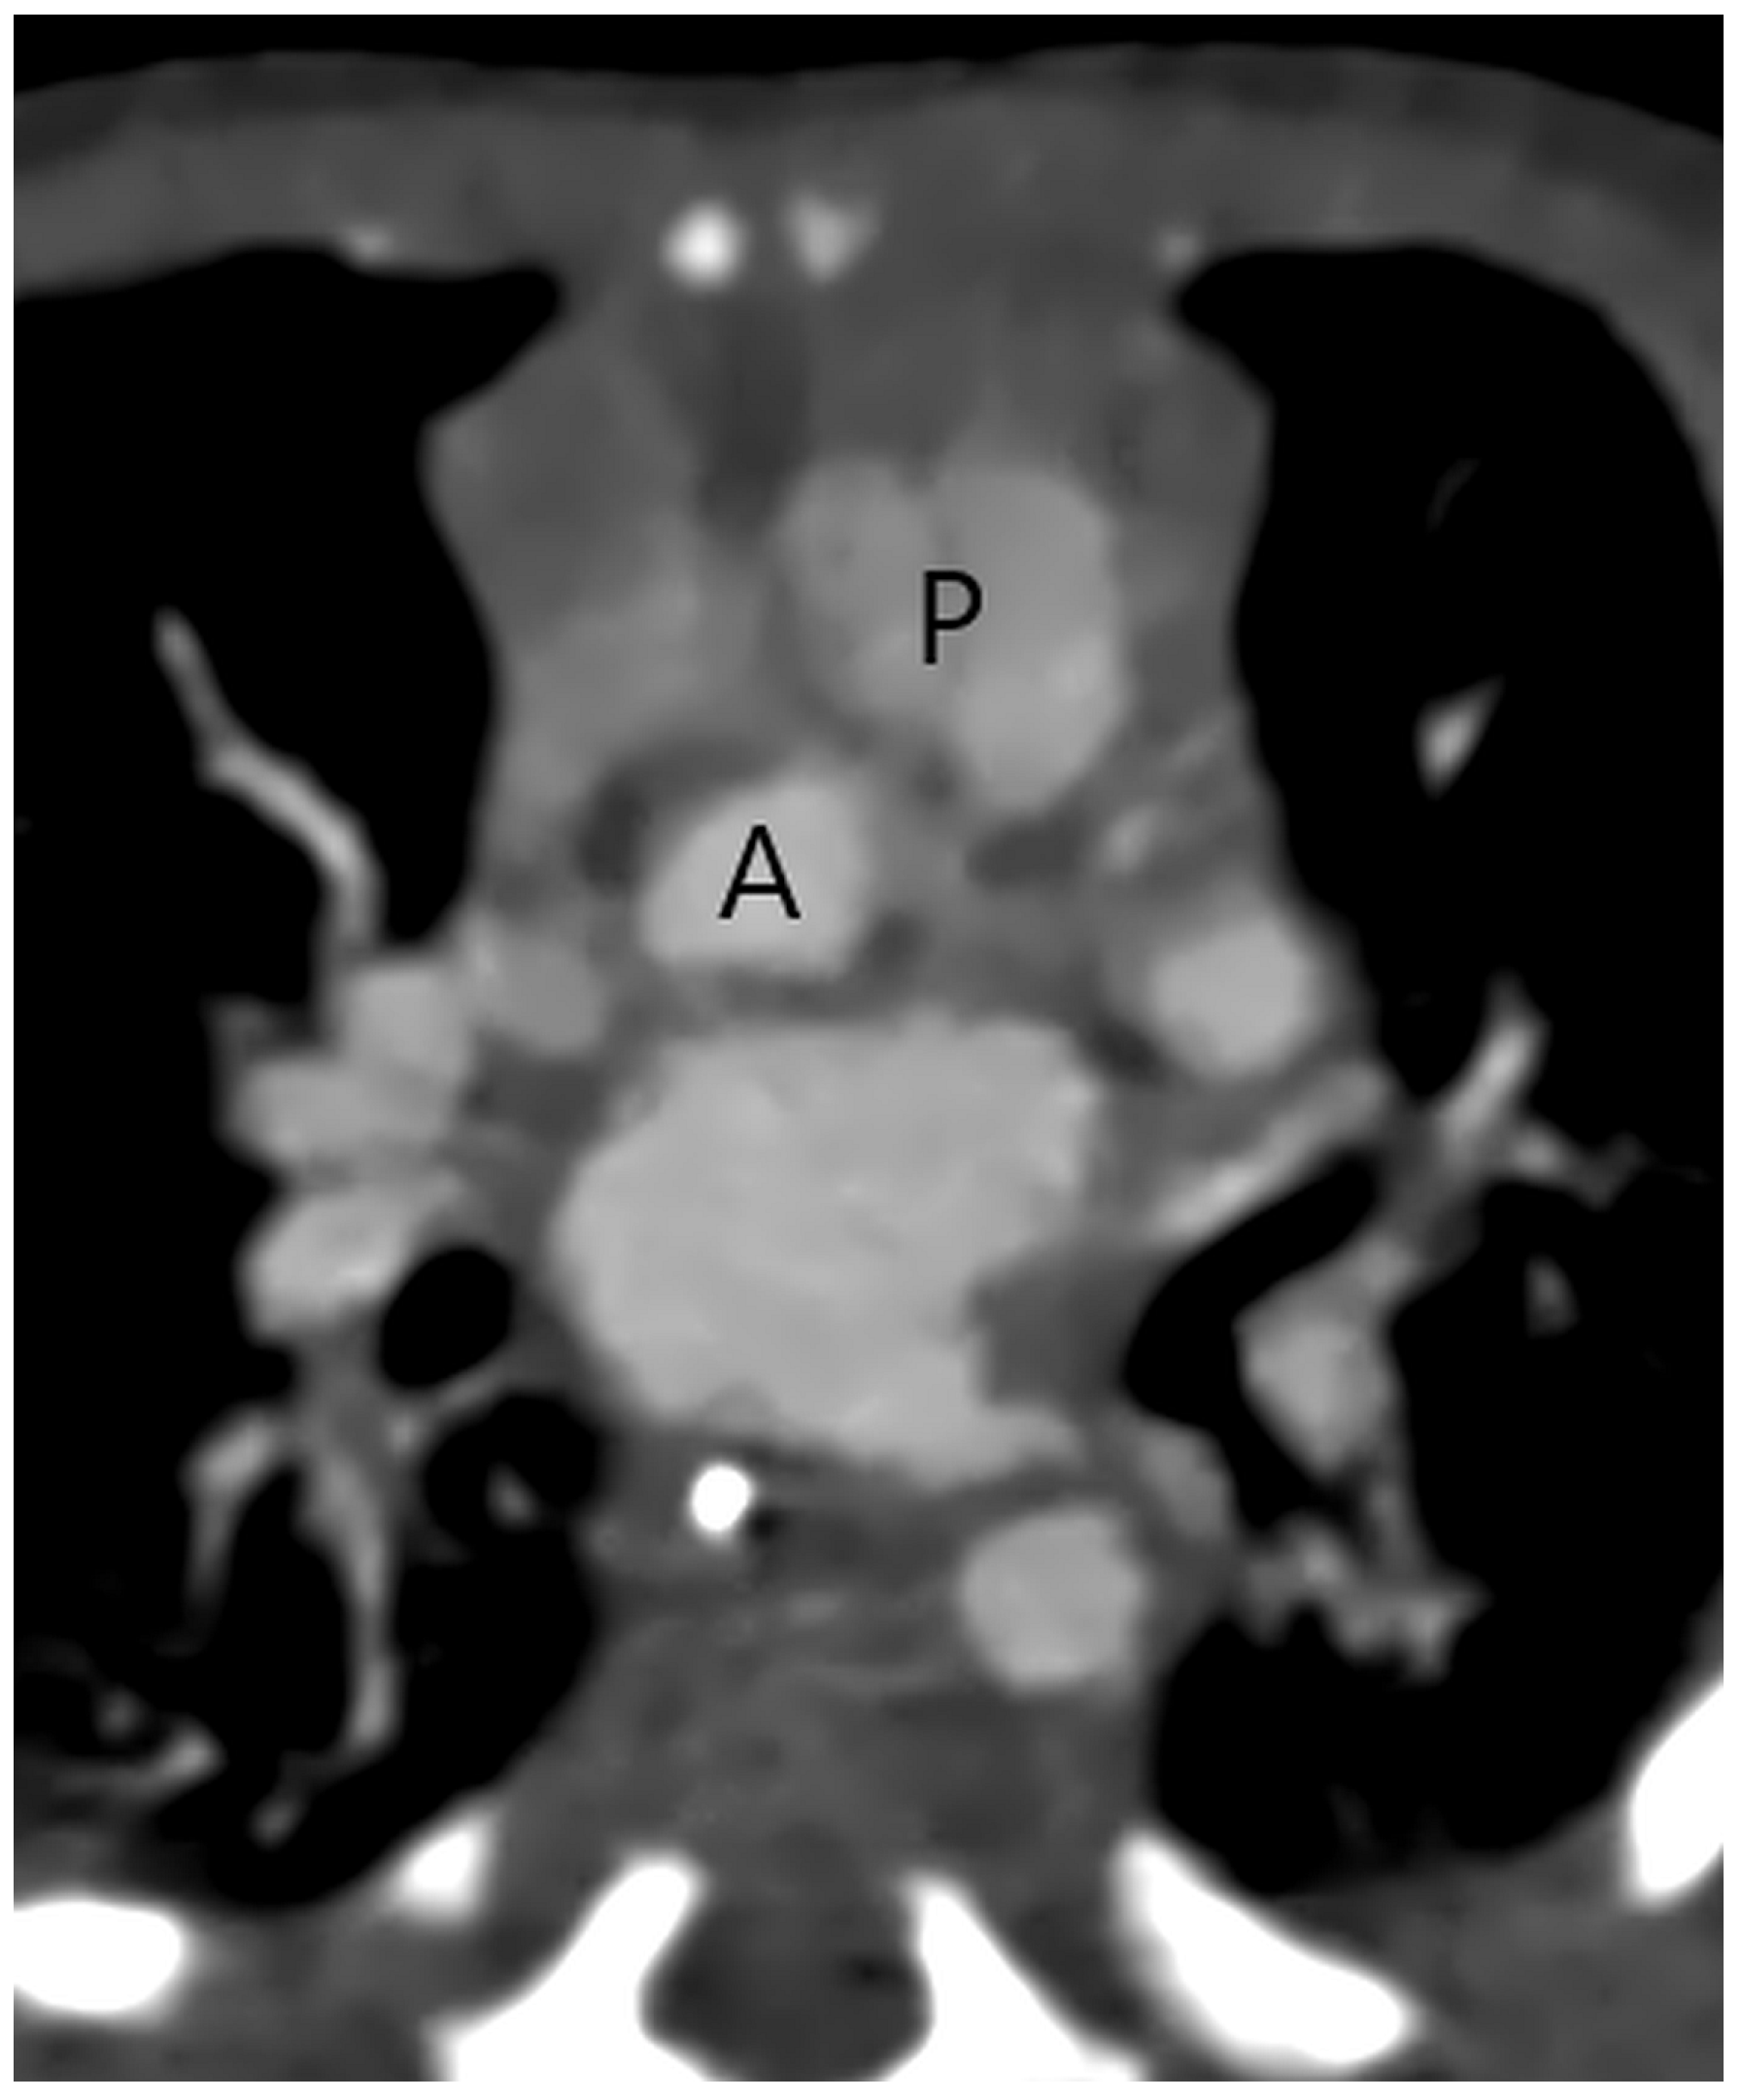

CT with its isotropic 3D imaging properties is an excellent tool for detailed morphological evaluation of aortopulmonary septal defect and assessment of other associated cardiovascular anomalies, enabling planning of surgical or interventional treatment. Firstly, in a patient with suspect APW, it is important to identify two separate semilunar (aortic and pulmonary) valves (Figure 1) to be able to differentiate APW from a common truncus arteriosus where a single truncal semilunar valve is present.

Figure 1.

A separate aortic (A) and pulmonary (P) valve in a patient with a type 2 aortopulmonary septal defect at CT angiography.